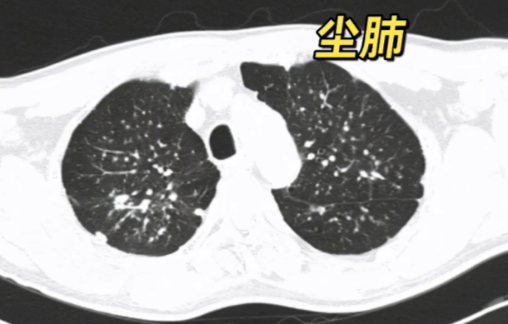

尘肺与矽肺是由于长期吸入含游离二氧化硅的粉尘所引起的肺部疾病。科学合理的饮食虽不能直接治疗疾病,但能够有效增强患者体质、缓解部分症状,是辅助康复的重要一环。以下是为患者整理的饮食与生活建议,供参考: